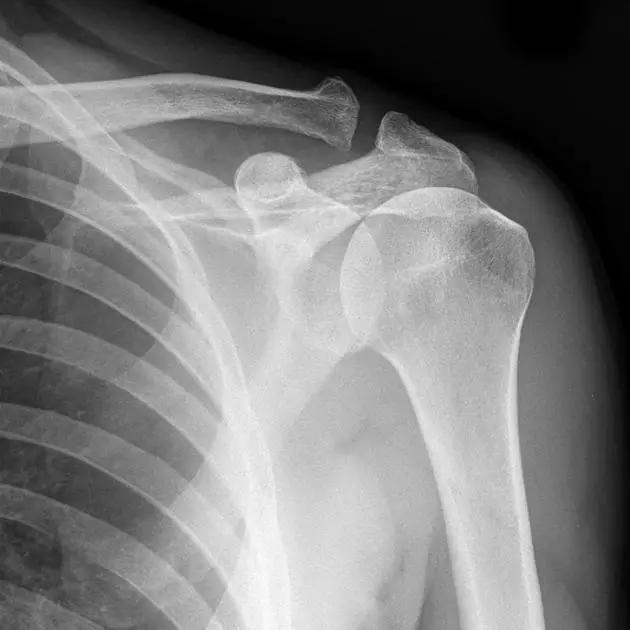

正常肩关节(来源:Radiopaedia)

1. Hill-Sachs 损伤和反 Hill-Sachs 损伤

肩关节脱位时,肱骨头和关节盂发生撞击,肱骨头表面凹陷性骨折。

- 肩关节前脱位时发生的肱骨头后外侧凹陷性骨折,是经典的 Hill-Sachs 损伤(Hill-Sachs lesion);

- 而肩关节后脱位时发生的肱骨头前内侧凹陷性骨折,是反 Hill-Sachs 损伤(Reverse Hill-Sachs lesion/ McLaughlin lesion)。